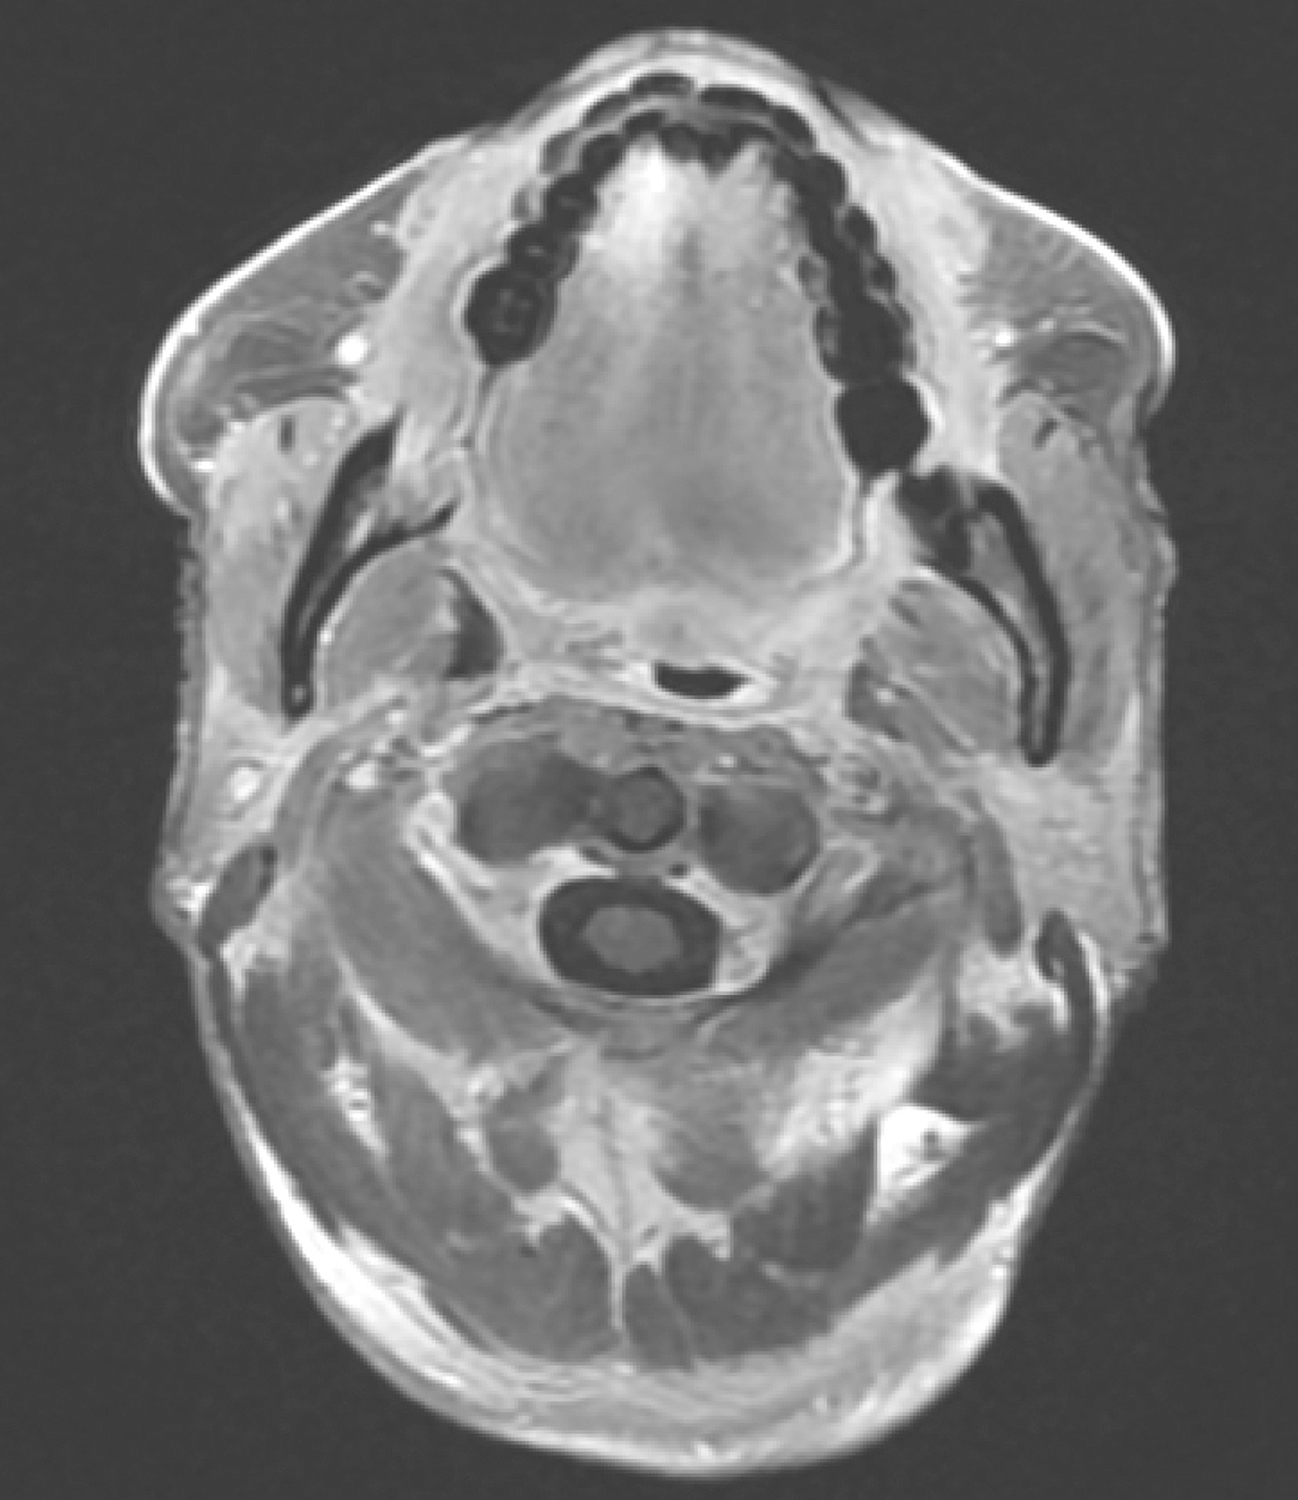

5.2016年10月19日口腔MRI

检查所见:

口咽左侧壁肿物,约2.3cm×1.8cm×2.3cm,T1WI呈等信号,T2WI/FS呈稍高信号,DWI扩散受限,增强扫描明显不均匀强化,肿物向外侵犯左侧咽旁间隙及左侧翼内肌,向下与左侧扁桃体关系密切(图4)。双侧颌下、颈深多发淋巴结,大者短径约0.8cm。

影像学诊断:

(1)口咽左侧壁肿物,考虑恶性,向外侵犯左侧咽旁间隙,贴邻左侧翼内肌,向下与左侧扁桃体关系密切。

(2)双侧颌下、颈深多发淋巴结,请随诊。

图4口腔MRI示口咽左侧壁肿物